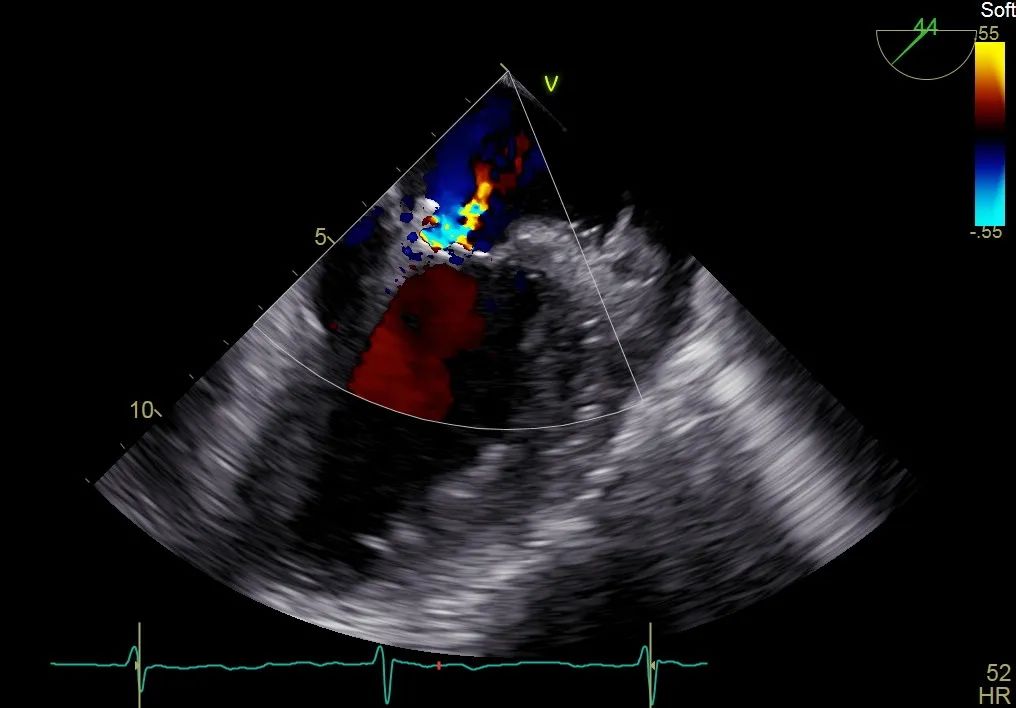

调整二尖瓣夹,使其定位于反流6-12点钟方位

二尖瓣在收缩期变成双孔状,反流有效减小